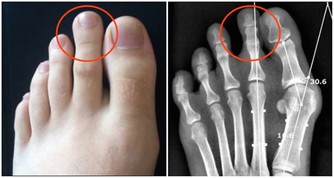

互相夾菜,會傳染胃病?

吃飯犯10個錯,傷胃又致癌! 一天三頓這麼吃,身體可能越吃越差

每次聚餐,菜餚豐盛活色生香,家人朋友頻頻舉箸夾菜,殊不知,一種叫幽門螺桿菌(Hp)的細菌可能在大快朵頤中彼此傳播。

Hp是人與人之間經口—口、胃—口傳播的,Hp感染者的唾液沾到菜餚上,取食者就有被Hp感染的可能。

不要小覷這種寄居於胃黏膜的細菌,它的致病性非同一般,已被確認是引發活動性胃炎、消化性潰瘍及胃癌的罪魁。

建議:聚餐最好使用公筷,杜絕Hp的感染和擴散。